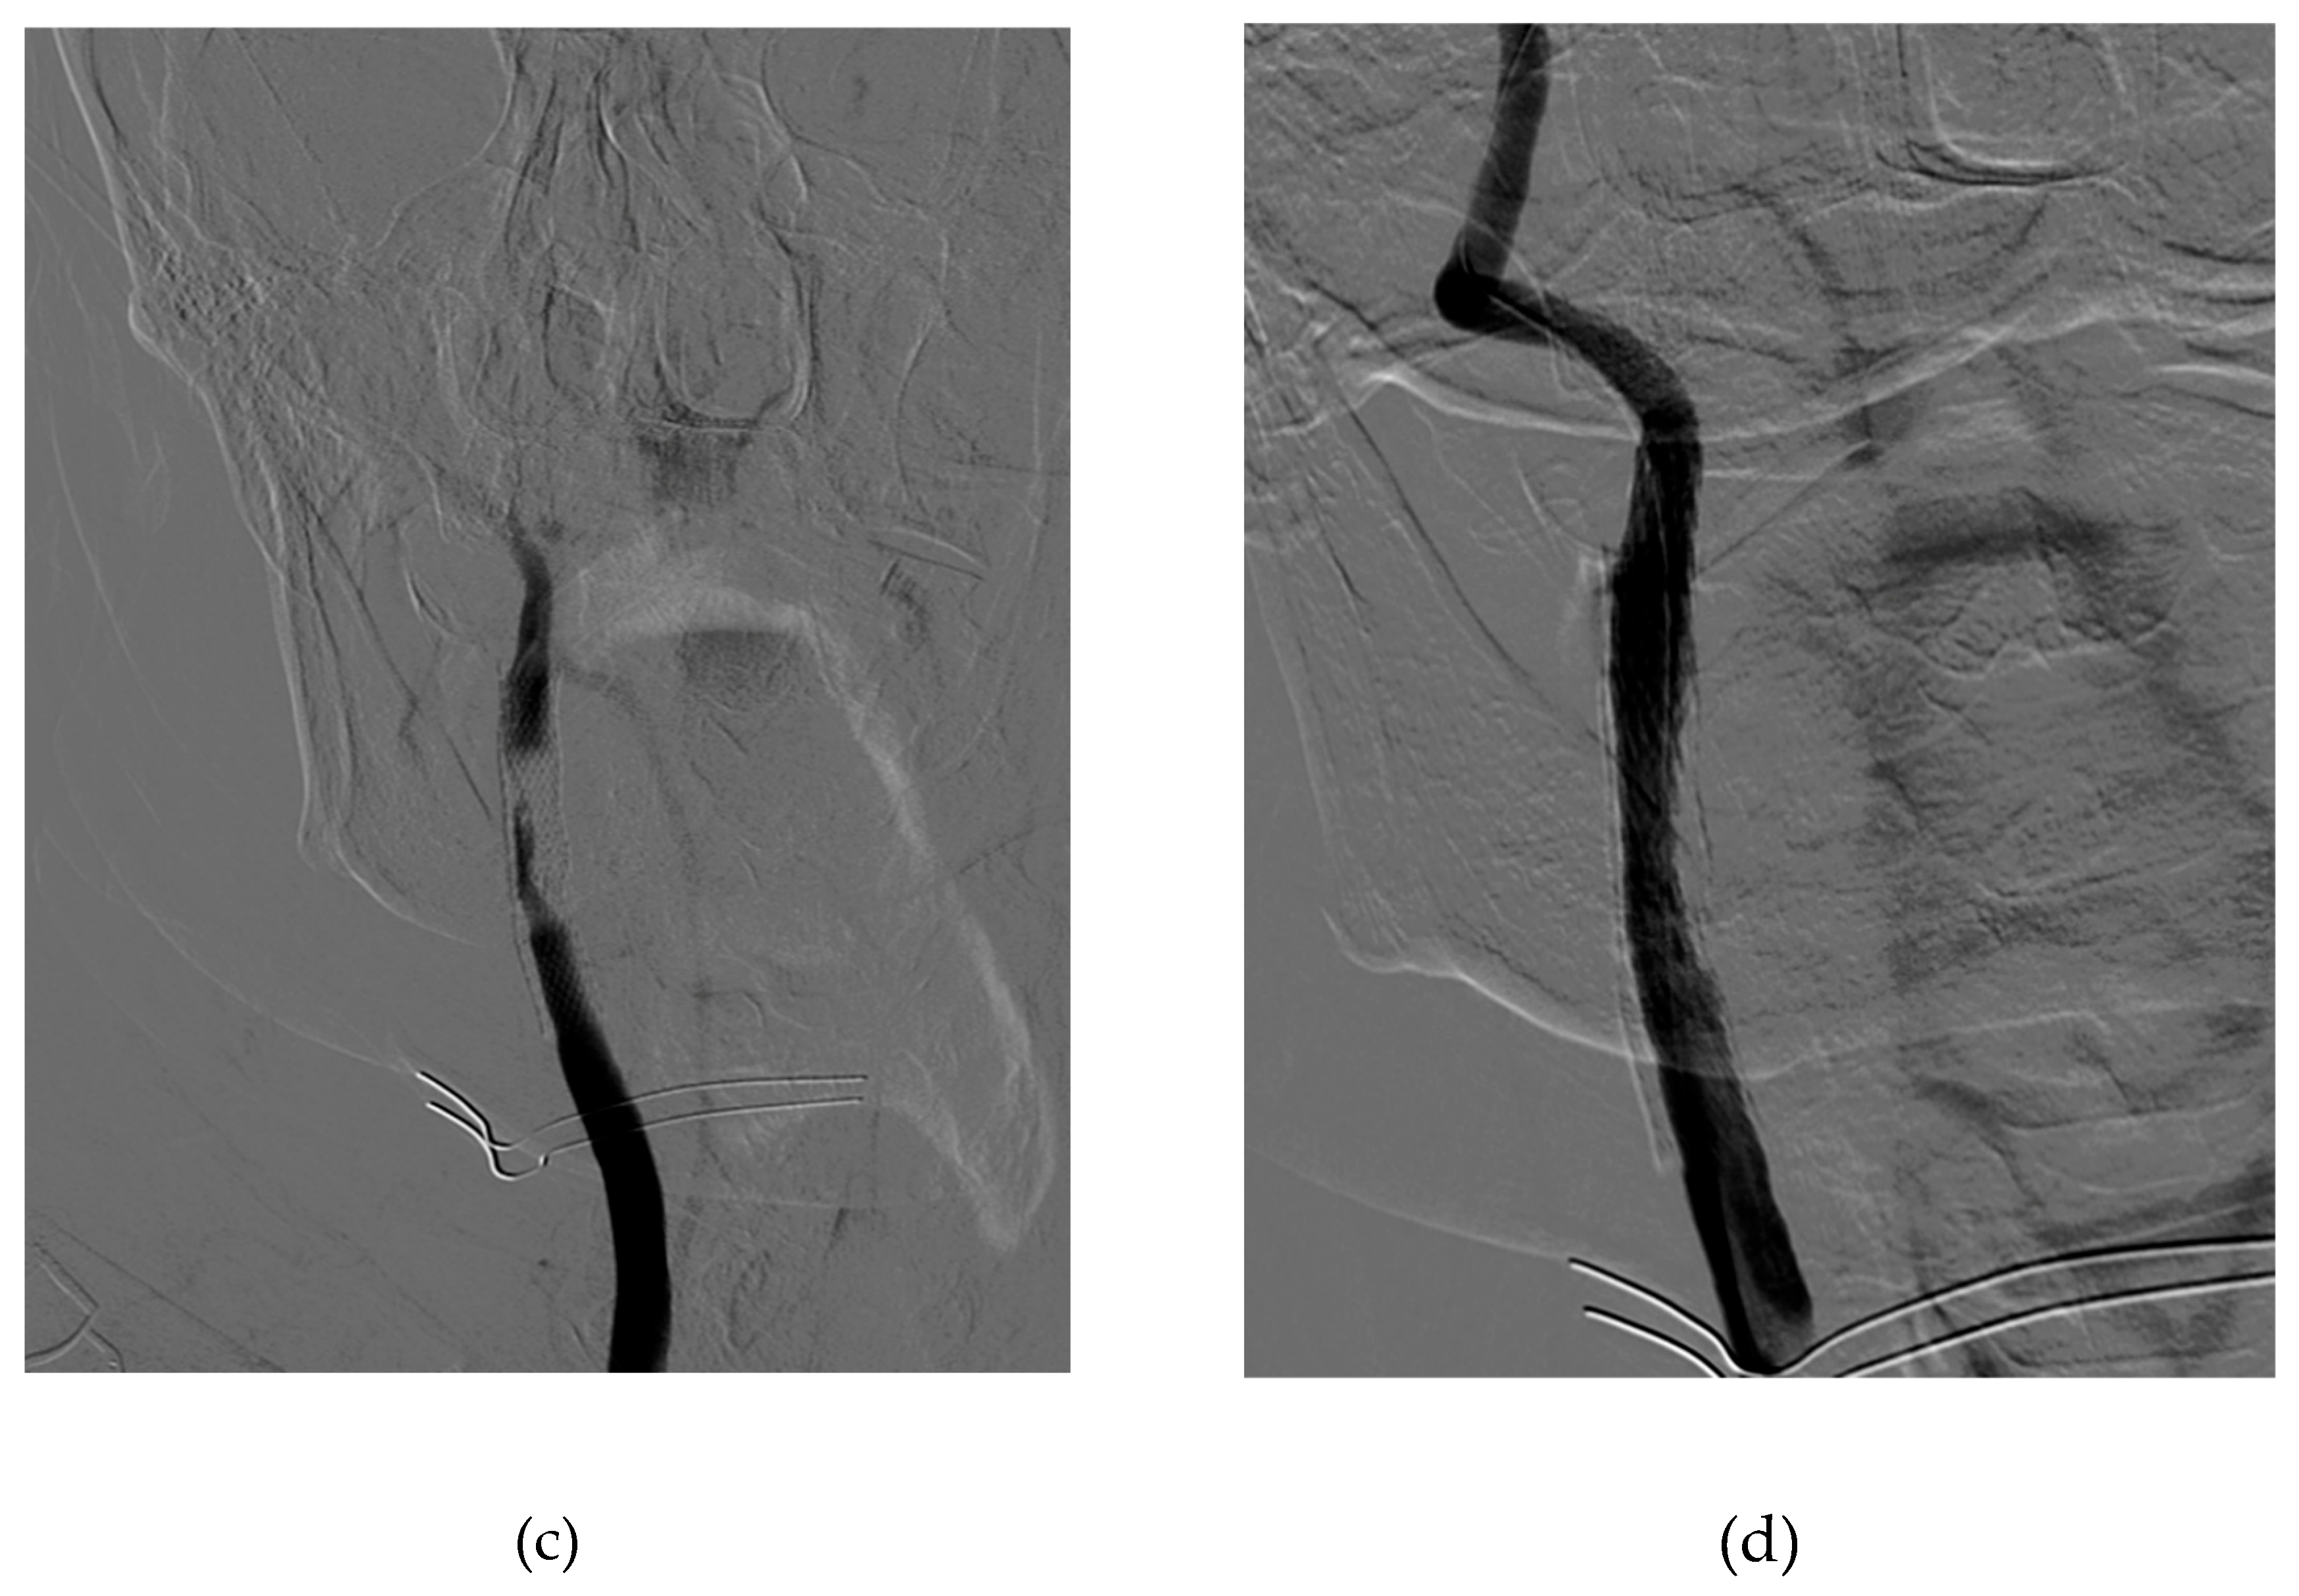

Figure 1. Procedural images: (a) basal symptomatic in-stent restenosis (b) result after drug-coated balloons (c) acute carotid stent thrombosis after the DEBalloon (d) Final result after CGuard MicroNet-covered stent implantation.

Unexpectedly, ten minutes later, the patient initiates a state of confusion along with left hemiplegia, deviation of the gaze, and the buccal rim. The neurological evaluation informed an NIH score of 21. The immediate angiographic control documented acute in-stent thrombosis and slow-flow compromising the ipsilateral intracranial circulation.

To tackle this emergency, an Epi-filter cerebral protection system was again placed, and a 9 x 40 mm micromesh stent (CGuard, InspireMD) was released slightly downstream from the end of the stenosed stent and gently post-dilated with a 5 mm balloon. The control angiography showed a resumption of the internal carotid flow with regular visualisation of the intracranial circulation.